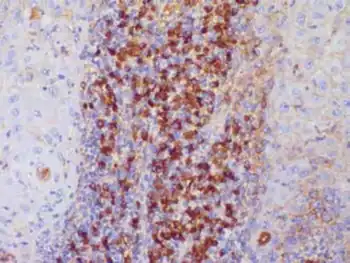

| Lobulated warty lesion affecting lower lip | |

Plasmoacanthoma is a condition of the oral mucosa characterized by a verrucous tumor with a plasma cell infiltrate.[1]: 797